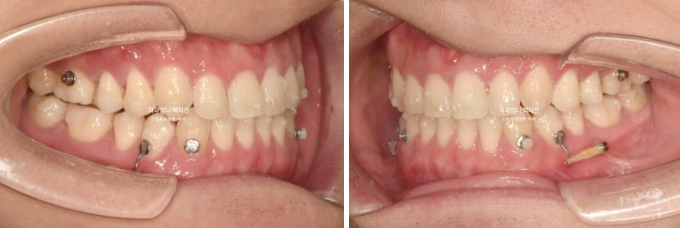

For improvement of the bite, midline, and premolar rotation, we went into a remaking phase, and from August to November 2024, the patient wore an additional set of aligners for 4 months.

24.11

The molar bite improved stably, but a very slight midline discrepancy remained, so we made one more additional set.

In total, the aligners were remade twice.

After wearing the aligners for another 3 months from December 2024 to February 2025, the treatment was completed.